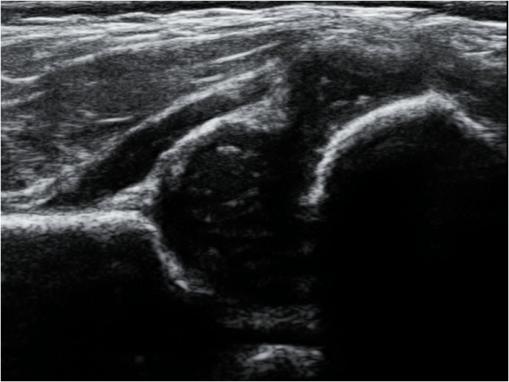

超声检车是患儿DDH筛查的首选检查方法。超声检查具有无创、无辐射、可重复检查、特异性及敏感性高等优势,能准确评估患儿髋关节发育情况(包括髋臼的发育、股骨头与髋臼的位置关系等),并能动态随访治疗效果。年龄≤6个月的患儿,首选超声检查排除DDH。